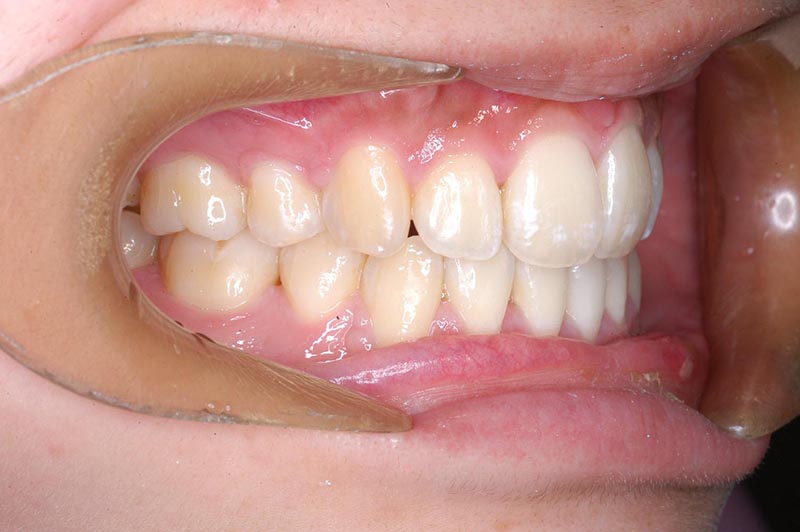

動的治療終了時

FP・IOP

批評・予后 上顎大臼歯のアンカーロスも生じず、大幅な前歯舌側移動、咬合の緊密化、歯根のパラレリングは行えた。上下口唇形態は改善し、良好なプロファイルが得られた。